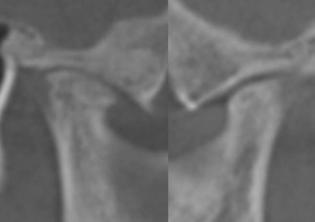

Figure 1 (left): A photo of a 69-year-old woman with a 2 mm anterior open bite and an excessive interlabial gap of 9 mm. Figure 2 (right): The sagittal slices of the above patient’s mandibular condyles reveal discontinuity of the cortical outline at the fossa and condyle (erosions). The altered condyles are flat along their path of function when she pushes her lower jaw forward to get the lips to touch in speaking, chewing, and breathing through her nose. Image captured using Dolphin® software (www.dolphinimaging.com)

Figure 3 (left): This same 69-year-old has undergone orthognathic surgery (bilateral sagittal split osteotomies and genioplasty) to close her open bite and shorten her anterior face height. This allows her lips to touch at rest and reduces energy usage to breathe, eat, and communicate. Figure 4 (right): The energy reduction at the mandibular condyles allows them to heal as evidenced by the recortication of the bone with the disappearance of the bony erosions. Image captured using Dolphin software (www.dolphinimaging.com)